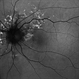

- Angioid Streaks

- 50 YEAR OLD FEMALE WITH NO SYSTEMIC ILLNESS WITH A CLASSICAL PICTURE. VISION REMAINS 6/6. THE FELLOW EYE HAS A SUBFOVEAL SCARRED CHOROIDLA NEOVASCULAR MEMBRANE.